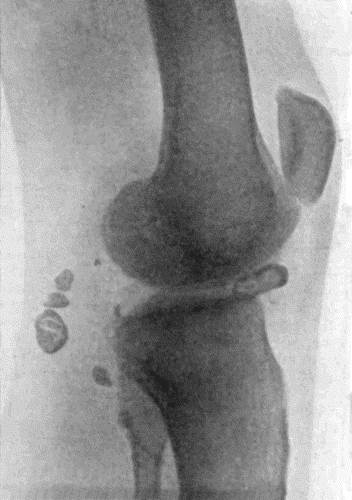

149.Central Sarcoma of Femur invading Knee Joint 495

150.Osseous Shell of Osteo-Sarcoma of Femur 495

151.Radiogram of Osteo-Sarcoma of Femur 496